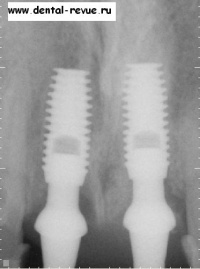

28. Диагностическая прицельная рентгенограмма переднего ряда верхней челюсти после операции перед установкой временных коронок.